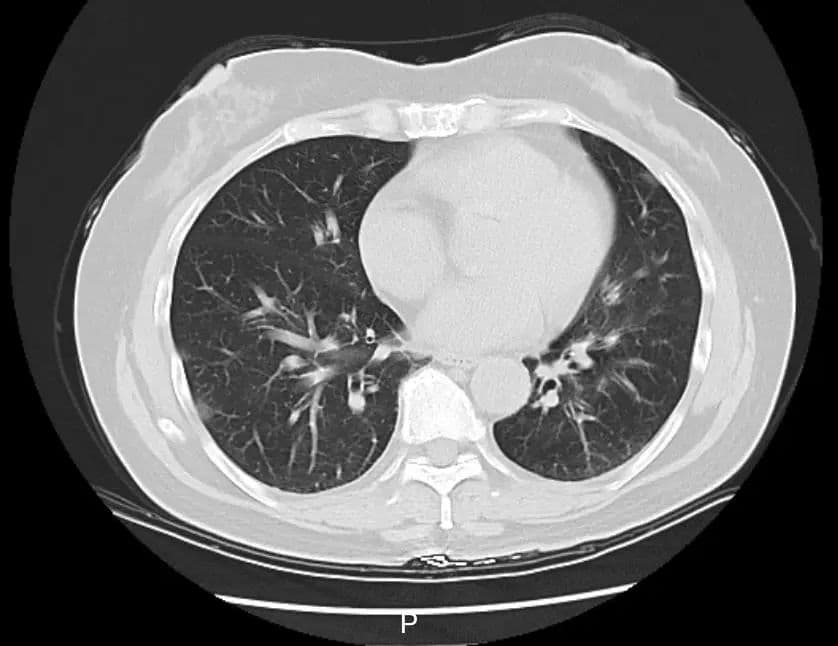

游客感染甲流后的肺部CT影像

另据1月13日,北京市疾病预防控制中心发布提示:当前,北京仍处于呼吸道传染病高发期,流感已达流行高峰,近期超98%流感病毒检测阳性的病例为甲型H1N1亚型流感病毒感染。

说起来,甲流的症状诸如咳嗽、喉咙痛、流鼻涕,伴随头痛和肌肉酸痛,很容易就令人联想起新冠初期的情景。